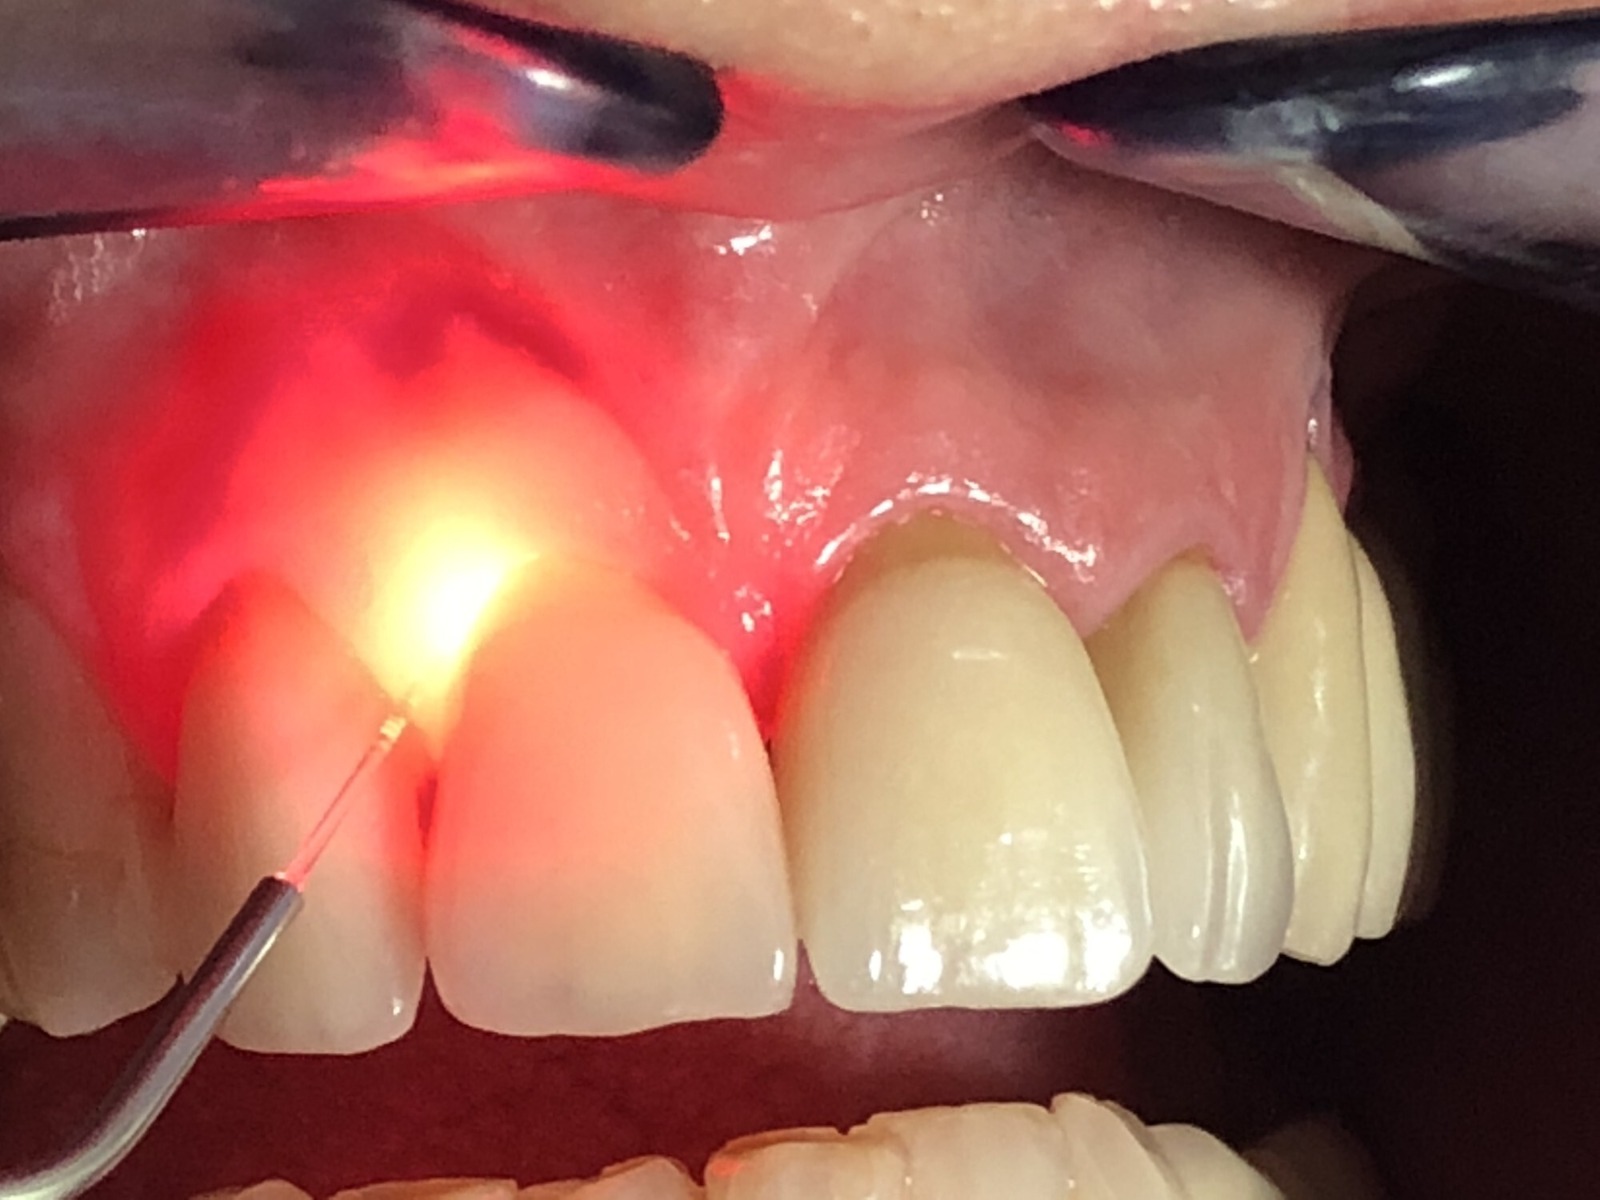

Is Laser Dentistry safe for gum treatment?

Yes. Laser dentistry is extremely safe and minimally invasive. At EndoElite, we use advanced dental lasers for gum surgery, depigmentation, and soft-tissue procedures with faster healing and minimal discomfort.